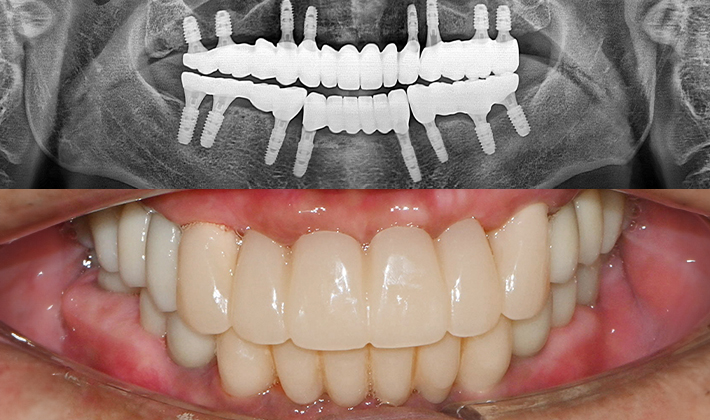

치과가 무서워 10년 동안 미뤄온 임플란트 수술 그 결과는?

2026.01.21